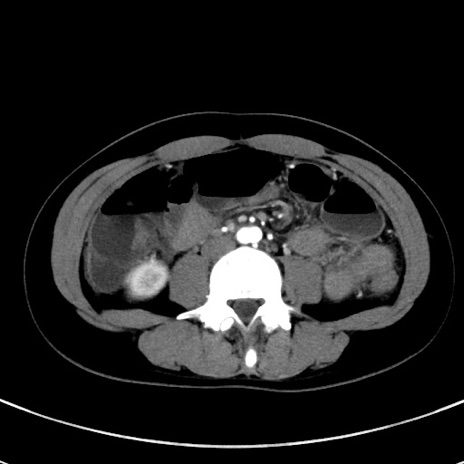

冠状断像

症例17(横断像)

【症例】20歳代女性

【主訴】嘔吐、下腹部痛

【現病歴】昨日夕食後に嘔吐し下腹部痛が出現。本日になっても嘔吐持続し改善しないため来院。

【身体所見】意識清明、BT 37.2℃、BP 108/67mmHg、腹部:平坦、やや硬、下腹部正中から右にかけて圧痛あり、反跳痛軽度あり、tapping pain(+)。

【データ】WBC 13600、CRP 14.94